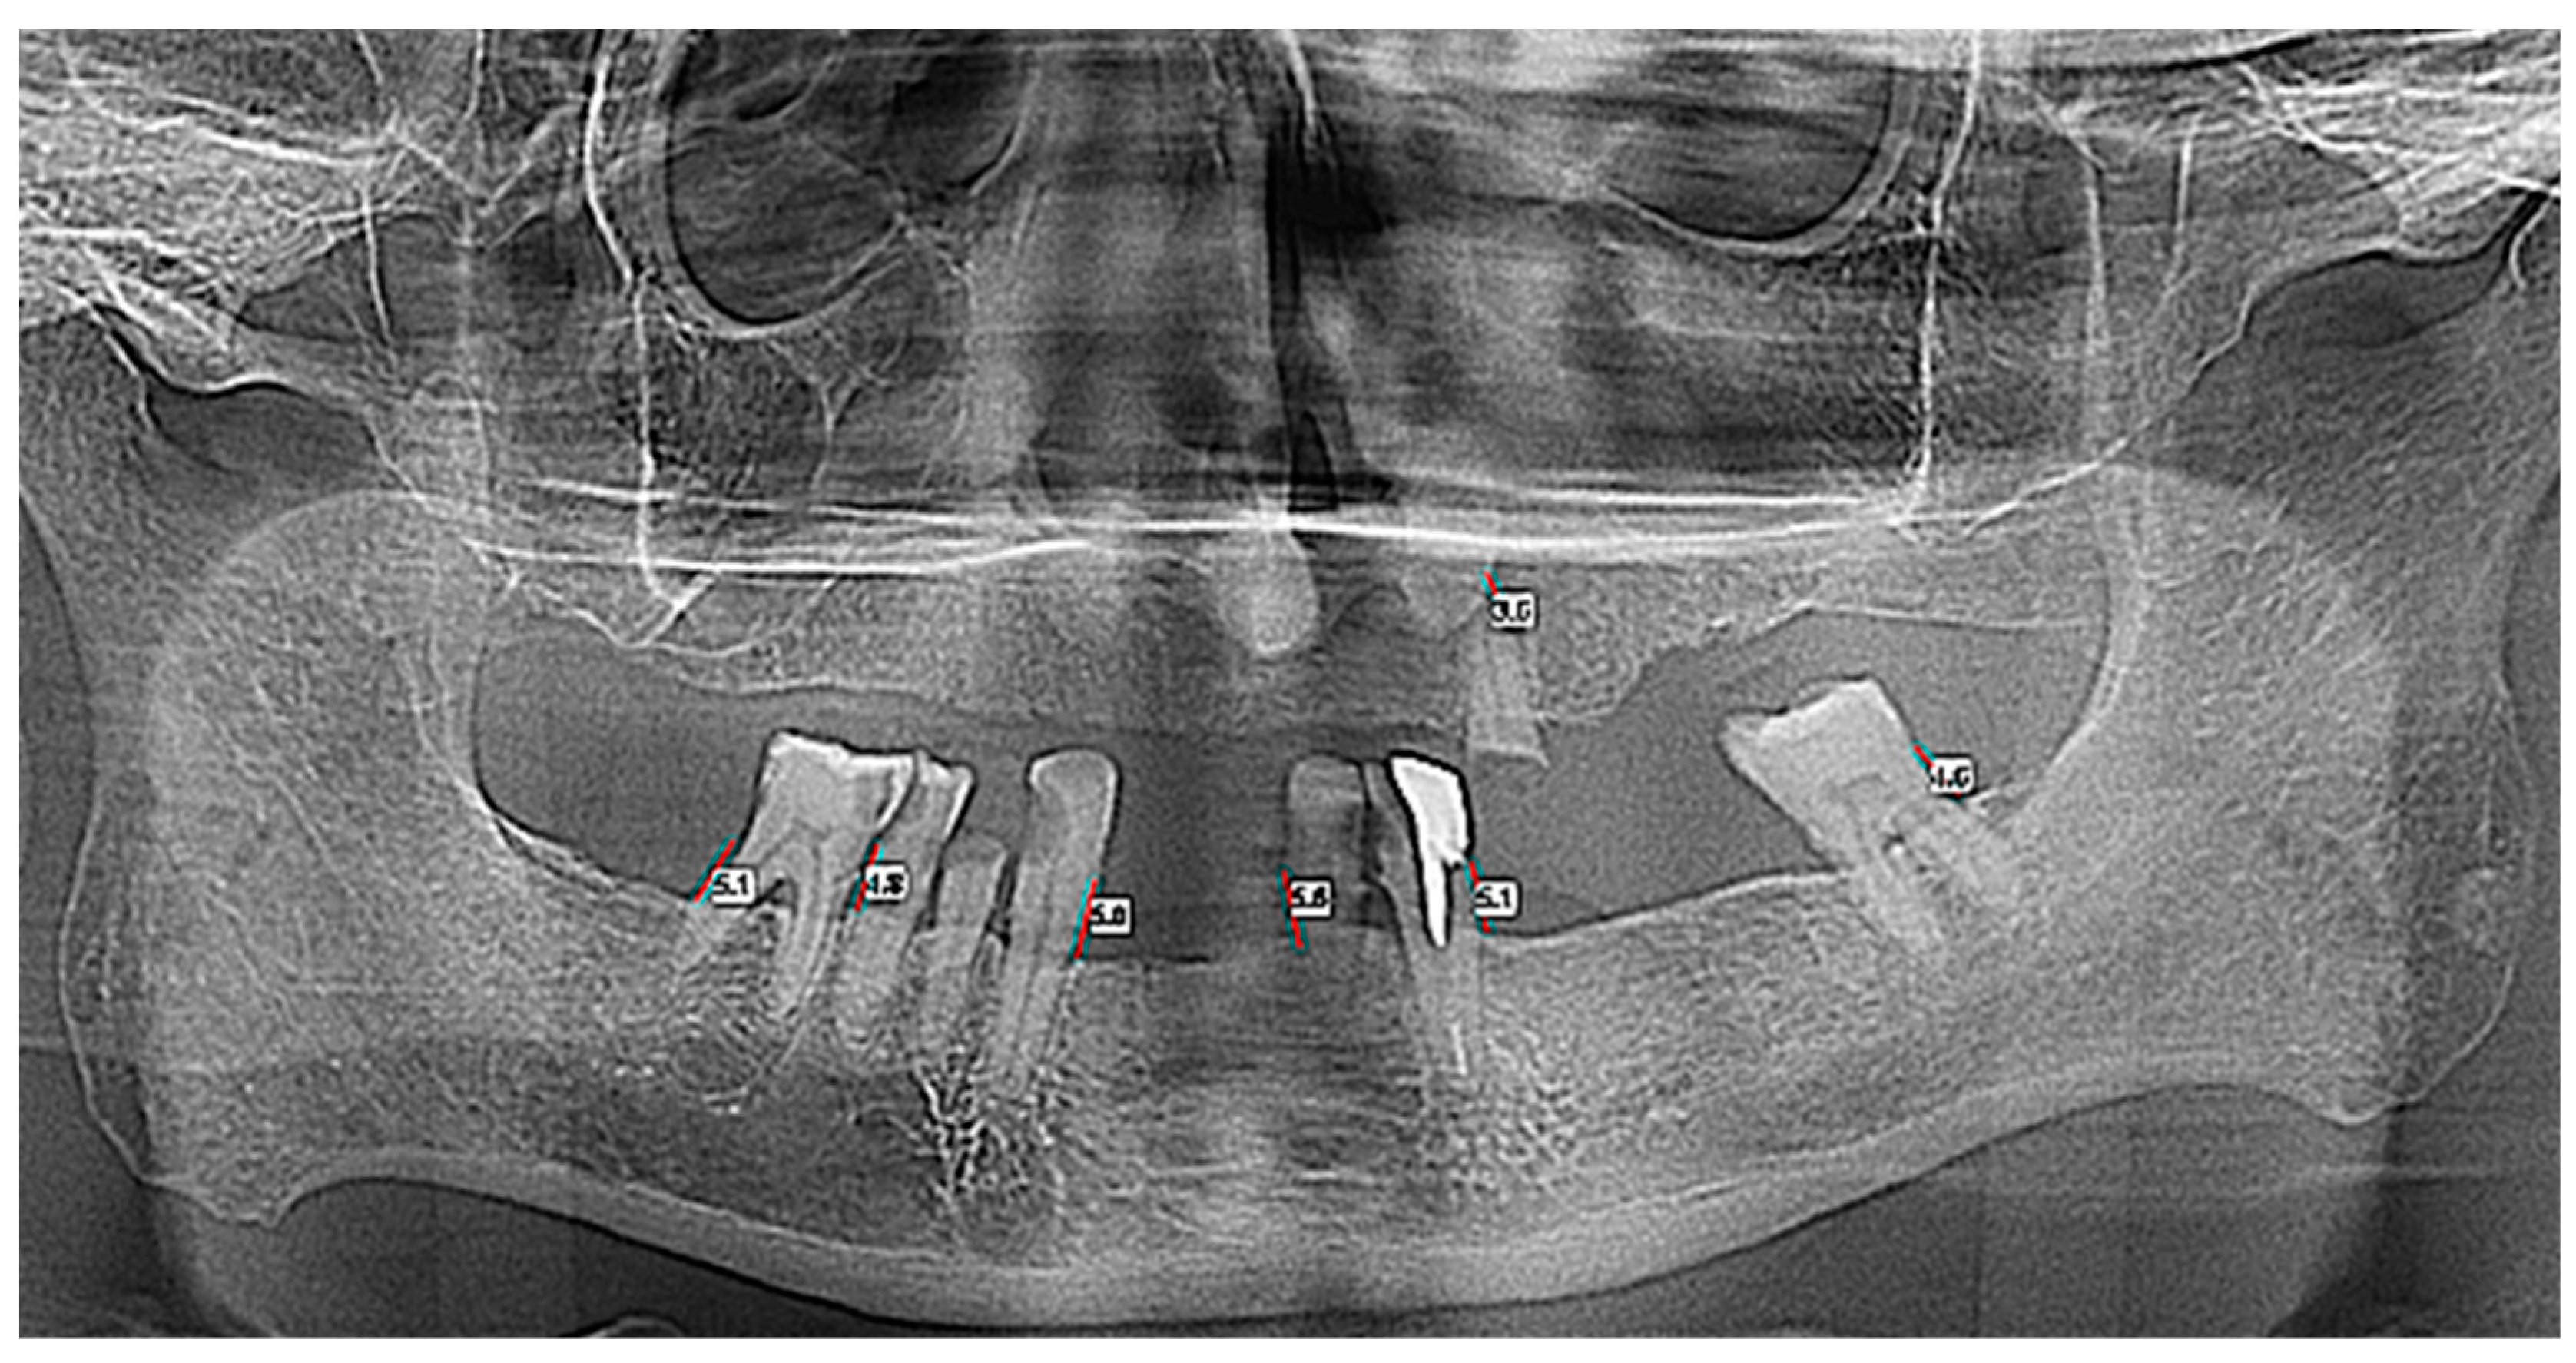

| Horizontal Bone Loss—Max Size | Group | Number | Mean | Standard Average Error | SD | Min | Max | Median | Student’s t Test |

|---|---|---|---|---|---|---|---|---|---|

| OPT | Control | 30 | 4.930 | 0.594 | 3.258 | 0.0 | 13.2 | 4.60 | t = −0.373 |

| ENT Cancer | 33 | 5.191 | 0.367 | 2.109 | 0.0 | 11.3 | 5.00 | p = 0.711 | |

| Total | 63 | 5.067 | 0.340 | 2.698 | 0.0 | 13.2 | 4.80 | ||

| CBCT 3D | Control | 30 | 5.736 | 0.633 | 3.471 | 0.0 | 14.10 | 5.75 | t = −0.548 |

| ENT Cancer | 33 | 6.152 | 0.438 | 2.519 | 0.0 | 12.40 | 6.17 | p = 0.586 | |

| Total | 63 | 5.954 | 0.377 | 2.992 | 0.0 | 14.10 | 6.00 |